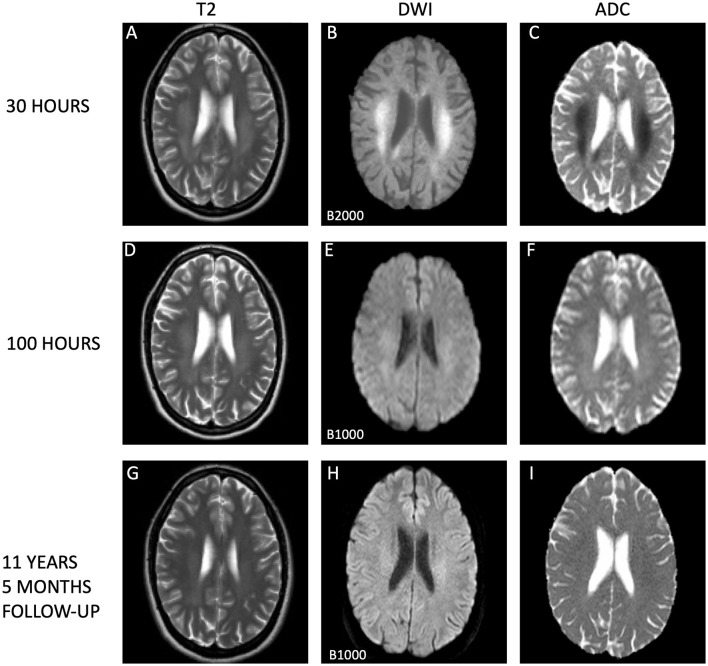

Cytotoxic lesions of the corpus callosum (CLOCC) are a clinicoradiological diagnosis, characterized by transient neurological symptoms and magnetic resonance imaging (MRI) changes in the splenium of the corpus callosum (SCC), which in most cases is completely reversible. However, the long-term pathophysiological trajectory and ultimate neurological outcomes of CLOCC remain largely unknown due to limited long-term follow-up data. We report an 11-year follow-up of a postpartum female with CLOCC, initially presenting with transient focal neurological symptoms and extensive diffusion-restricted white matter involvement including the SCC and surrounding area with diffusion restriction and low apparent diffusion coefficient values, indicative of cytotoxic edema. The edema regressed in days; over the years, she remained asymptomatic despite persistent white matter changes on MRI in the centrum semiovale. This case challenges the view of CLOCC as completely reversible and raises questions regarding the significance of lasting white matter changes. The enduring absence of neurological symptoms and stable radiological profile throughout the decade underscores the singular nature of CLOCC and the lasting, though isolated, impact on white matter. This report contributes a crucial perspective, suggesting that CLOCC may involve just an isolated episode without recurrent events or progressive neurological decline. By offering the first longitudinal analysis of a CLOCC episode with an extended follow-up of over a decade, our case enhances current knowledge about the long-term neurological and radiological landscape of this condition. It suggests a reevaluation of the conceptual understanding of CLOCC as an entirely reversible, non-relapsing disorder, highlighting the need for further research into its long-term impacts on cerebral white matter integrity.

胼胝体细胞毒性病变(CLOCC)是一种临床放射学诊断,其特征是短暂的神经系统症状和胼胝体(SCC)脾脏的磁共振成像(MRI)改变,在大多数情况下是完全可逆的。然而,由于长期随访数据有限,CLOCC的长期病理生理轨迹和最终神经学结局在很大程度上仍然未知。我们报告了一名产后CLOCC女性患者的11年随访,最初表现为短暂的局灶性神经症状和广泛的弥漫性白质受累,包括SCC和周围区域,弥漫性受限和低表观弥漫性系数值,表明细胞毒性水肿。水肿逐渐消退;多年来,尽管MRI显示半骨正中持续出现白质改变,但患者仍无症状。该病例挑战了CLOCC是完全可逆的观点,并提出了关于持久白质变化的重要性的问题。在整个十年中,神经系统症状的持续消失和稳定的放射学特征强调了CLOCC的独特性和对白质的持久影响,尽管是孤立的。该报告提供了一个至关重要的观点,表明CLOCC可能只是一个孤立的发作,没有复发事件或进行性神经功能衰退。通过首次对CLOCC发作进行纵向分析,并进行了超过十年的随访,本病例增强了当前对该疾病长期神经学和放射学的认识。该研究建议重新评估CLOCC作为一种完全可逆、非复发性疾病的概念理解,并强调需要进一步研究其对脑白质完整性的长期影响。